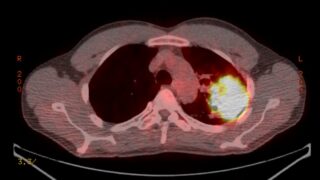

臓器の病理(整理中) 病気三昧の人生が、今の私をつくってくれた ——小児喘息から肺がんへ。しんどかった日々がホメオパスへの道を開いた 病気三昧の人生が、今の私をつくってくれた——小児喘息から肺がんへ。しんどかった日々がホメオパスへの道を開いた皆様こんにちは 高普段着ホメオパスの川崎です。いつもはレメディや症状のことをお伝えすることが多いけど、今回はちょっと趣向を変えて、僕... 2026.03.17 その他臓器の病理(整理中)